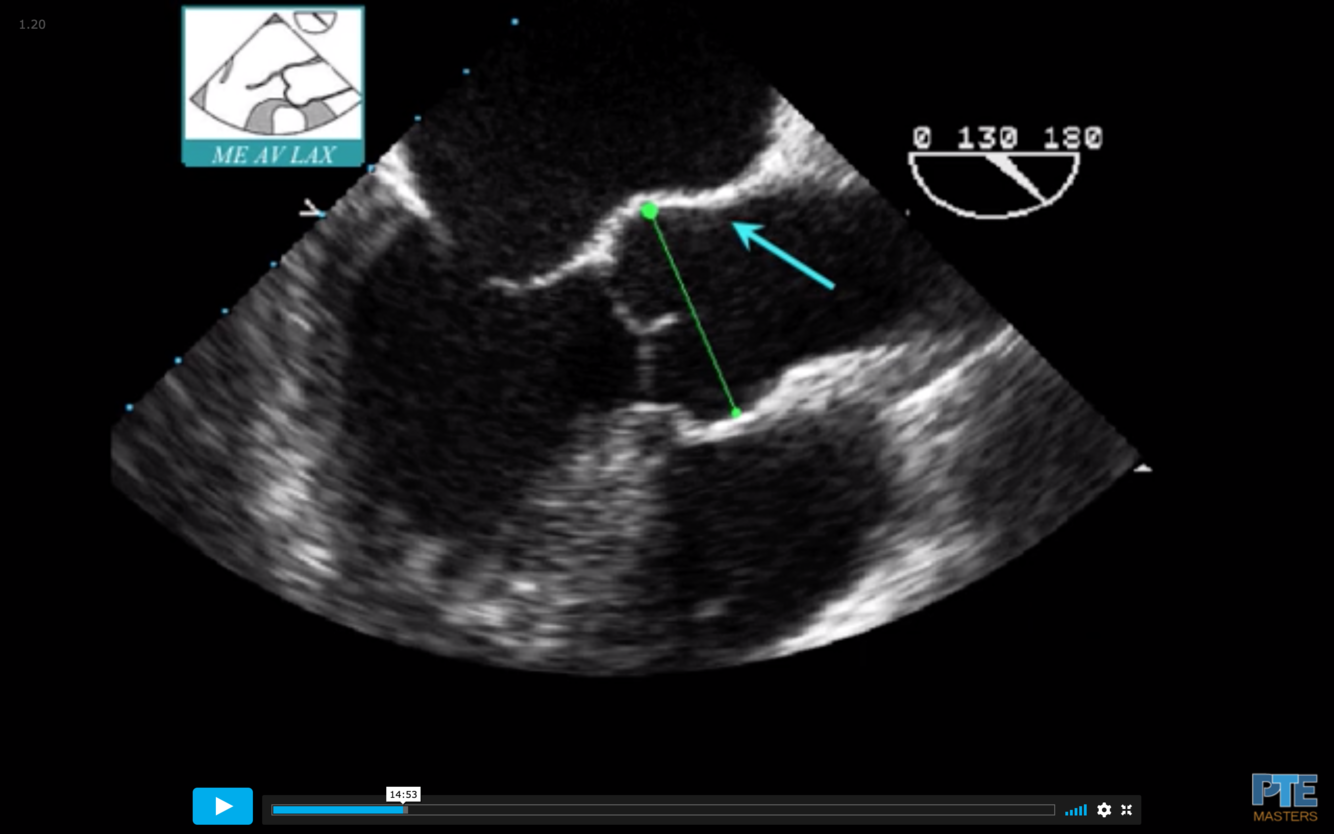

What is the measurement seen here?

Sinus of Valsalva

What is the blue arrow indicating?

Sinotubular Ridge or Sinuotubular Junction